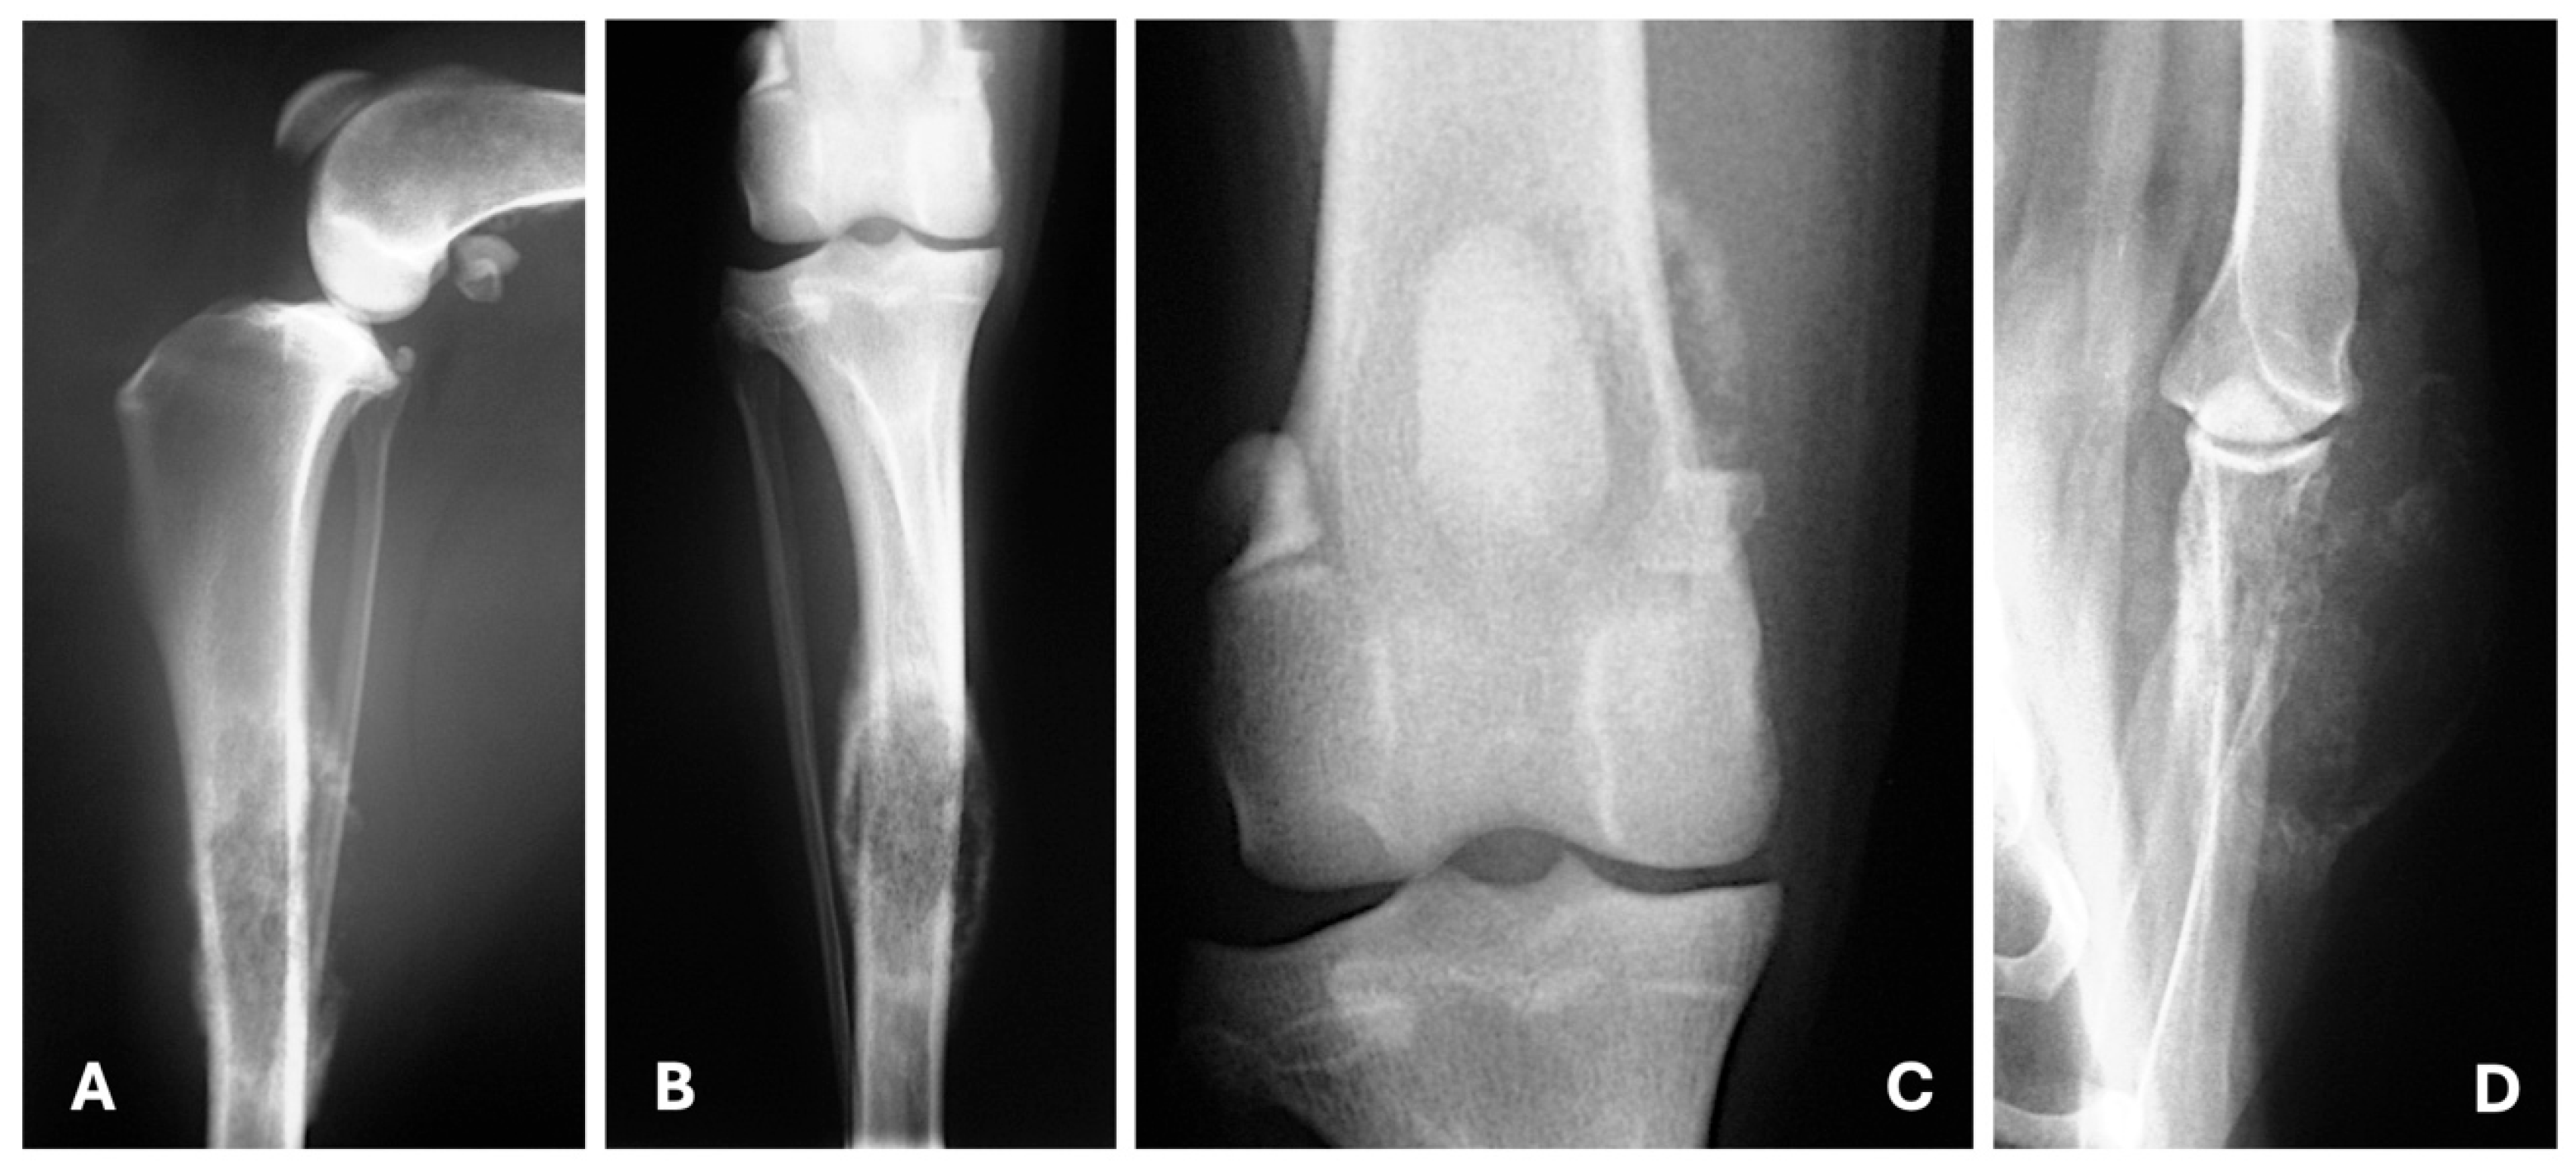

4.1. Radiography

- Baptista, C.S.; Santos, A.A.; Villagrasa, M.H.; Matos, A.J. Diagnostic Imaging Findings of Uncommon Sites for Distant Metastasis in Canine Mammary Tumours—Abstracts from the annual meeting of the european college of veterinary diagnostic imaging and european association of veterinary diagnostic imaging. Vet. Radiol. Ultrasound. 2014, 55, 651–679. [Google Scholar] [CrossRef]